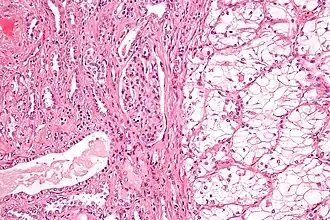

| Micrografia de tecido renal. À direita: carcinoma de células renais do subtipo de células claras, o subtipo mais comum. À esquerda: tecido normal sem cancro. | |